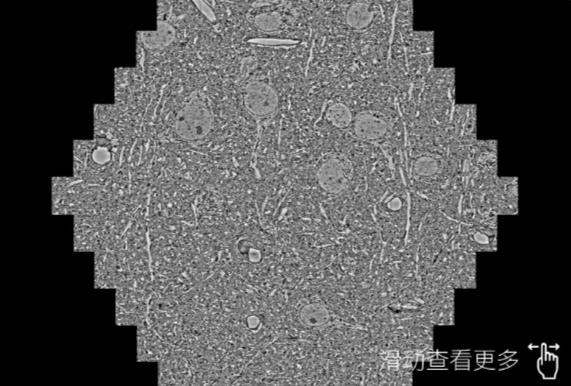

鼠脑切片。左图使用邢台蔡司邢台扫描电镜MultiSEM706对165μmx143pm面积区域成像,耗时仅需1.5秒。右图为鼠脑切片中30μm区域放大效果。样品由芝加哥大学B.Kasthuri提供。

使用蔡司高速邢台扫描电镜MultiSEM对1mm²人脑皮层组织进行高分辨成像,并对其中的各种细胞结构进行三维重构分析。左图展示了2x3mm²组织平面中锥体神经元的三维重构效果。右图显示了局部体积神经元三维重构。图像由哈佛大学chtman实验室提供,渲染图由D. Berger 制作。